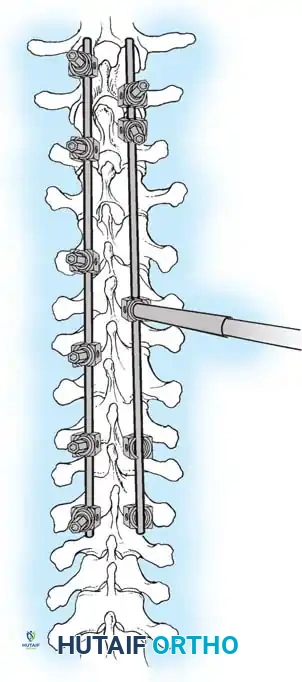

Posterior Surgeries for Idiopathic Scoliosis: A Masterclass in Surgical Technique

The posterior approach remains the workhorse for the surgical correction of adolescent idiopathic scoliosis. It provides extensile, safe access to the entire vertebral column, facilitating multi-segmental instrumentation and robust arthrodesis. Success relies on meticulous patient positioning to preserve sagittal alignment, precise subperiosteal exposure to minimize blood loss, and rigorous facetectomy and decortication to ensure a solid, long-lasting spinal fusion.

The posterior approach to the spinal column remains the most universally utilized and versatile corridor for the surgical management of adolescent idiopathic scoliosis (AIS). Familiar to all fellowship-trained orthopaedic spine surgeons, this extensile approach offers safe, comprehensive exposure of the entire vertebral column. It facilitates the application of modern multi-segmental pedicle screw constructs, allows for aggressive posterior column osteotomies, and provides a massive surface area for robust arthrodesis.

2. Biomechanical Stability: Rigid segmental instrumentation to neutralize micromotion.